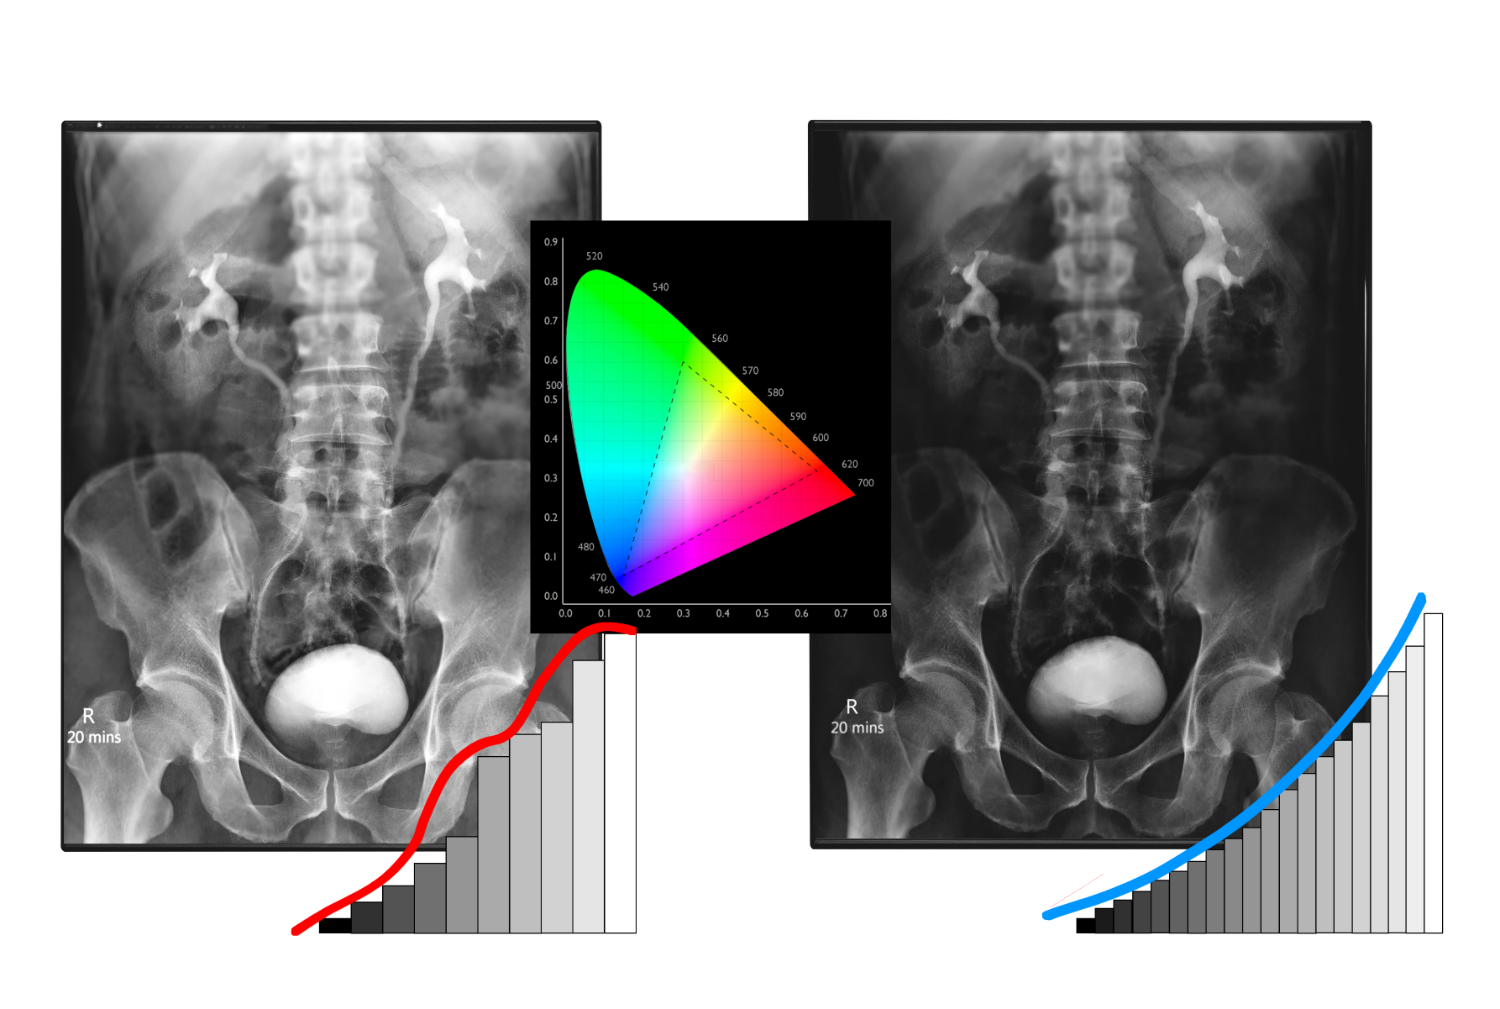

什麼是DICOM

DICOM,即醫學數位成像和通信(Digital Imaging and Communications in Medicine),是一個在醫療領域廣泛應用的標準協議。我們的醫療顯示器遵從DICOM標準,這意味著它能夠有效地處理、傳輸和顯示醫學影像及相關信息。 DICOM標準確保了不同醫學影像設備和軟體系統之間的一致性和互通性。這對於醫療行業至關重要,因為它確保了醫生、技術人員和其他相關專業人員能夠順暢地共享和解讀患者的醫學影像。DICOM標準的採用有助於提高醫學影像的品質、一致性和可比性,同時確保患者的診斷和治療過程更為精確和高效。

醫療顯示器校正

我們提供的醫療顯示器校正技術是放射學、內視鏡檢查、超音波、牙科、醫療手術、顯微鏡,以及各種醫學影像應用(包括獸醫)的最佳解決方案。

顯示器校正不僅僅是技術層面的提升,更是對醫學影像準確性的承諾。這項技術保證您在各種醫學場景中都能得到最優質的影像表現,從而提高醫療診斷和手術的精確性。

透過我們的醫療顯示器校正,您可以確保顯示器呈現出最真實、最清晰的醫學影像,無論是進行放射學檢查還是進行微小手術。我們致力於提供高標準的顯示效果,以滿足醫療領域對精準度和可靠性的嚴格要求。